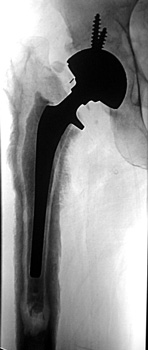

Arthrographic evidence of looseningcontrast enters

abnormally widened interface Gruen zone 1 and 2

Arthrographic evidence of cup looseningcontrast enters

abnormally widened interface Gruen zone II and III